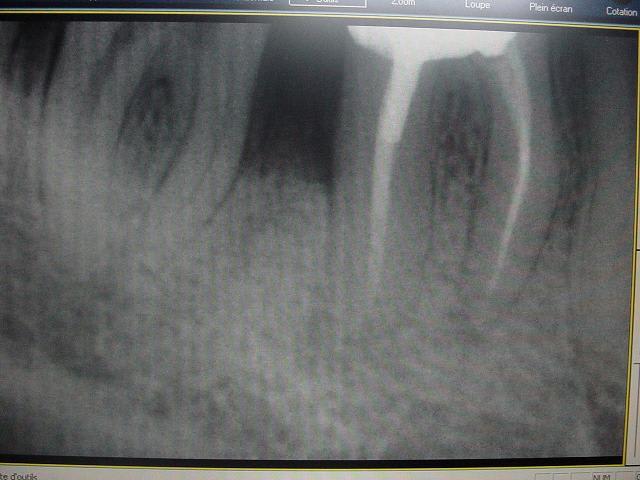

voici un cas paro qui me pose problème: Homme 39 ans, non fumeur, exellente santé ( spotif +++). PAJ dans un mauvais contexte occlusal ( bout à bout et contact essentiellement en posterieur. Je suis un peu paumé sur ce coup là! surtout sur le devenir des molaires. Des pistes avant d'en parler à nice? merci

ci joint des retro de mars 2001 et aout 2003 de 46 qui montre l'evolution du cas..